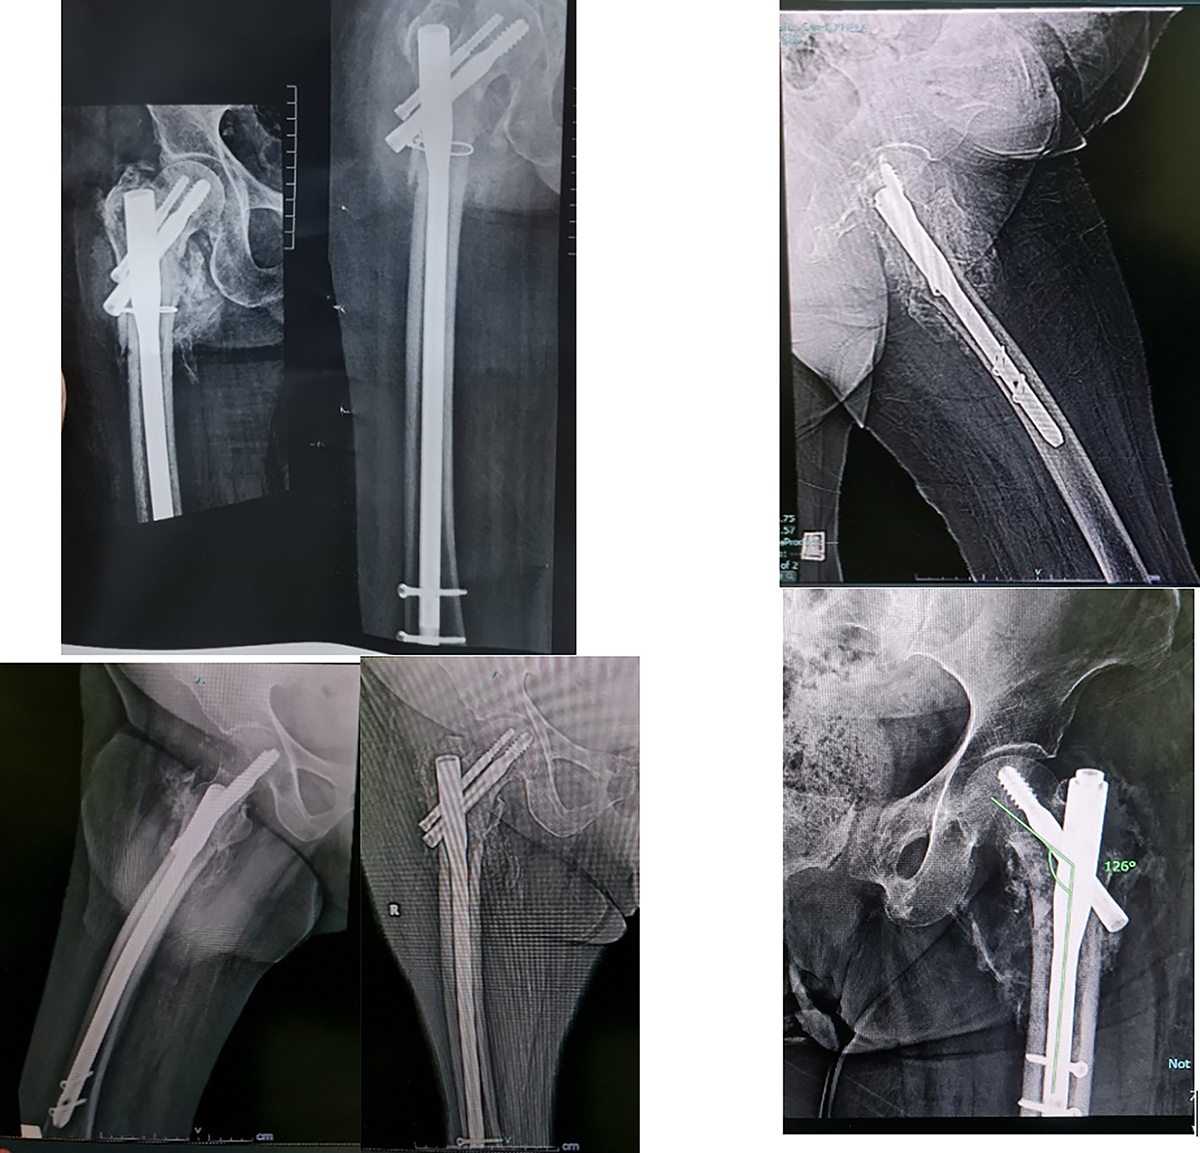

Figure 3

Heterotrophic ossification.